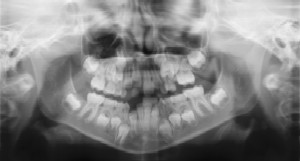

Radiographs (X-Rays) are a vital and necessary part of your child’s

dental diagnostic process. Without them, certain dental conditions can

and will be missed.

Radiographs detect much more than cavities. For example, radiographs may be needed to survey erupting teeth, diagnose bone diseases, evaluate the results of an injury, or plan orthodontic treatment. Radiographs allow dentists to diagnose and treat health conditions that cannot be detected during a clinical examination. If dental problems are found and treated early, dental care is more comfortable for your child and more affordable for you.

The American Academy of Pediatric Dentistry recommends radiographs and examinations every six months for children with a high risk of tooth decay. On average, most pediatric dentists request radiographs approximately once a year. Approximately every 3 years, it is a good idea to obtain a complete set of radiographs, either a panoramic and bitewings or periapicals and bitewings.

Pediatric dentists are particularly careful to minimize the exposure of their patients to radiation. With contemporary safeguards, the amount of radiation received in a dental X-ray examination is extremely small. The risk is negligible. In fact, the dental radiographs represent a far smaller risk than an undetected and untreated dental problem. Lead body aprons and shields will protect your child. Today’s equipment filters out unnecessary x-rays and restricts the x-ray beam to the area of interest. High-speed film and proper shielding assure that your child receives a minimal amount of radiation exposure.